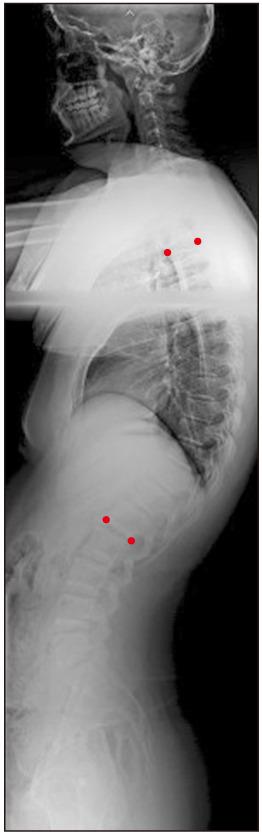

北约旦 50°-65° Cobb 角 Scheuermann 后凸畸形患者的生活质量评估:一项前瞻性对比研究。

Assessment of Quality of Life for Scheuermann's Kyphosis Patients with Cobb's Angle 50°-65° Treated Conservatively or Surgically in North Jordan: A Prospective Comparative Study.

Scheuermann's disease is the most common cause of hyperkyphosis of the thoracic spine during the adolescence period. It causes neck and lower back pain, restriction of lung expansion, traction of the spinal cord, increased vulnerability to vertebral fracture, and a hump. Patients with curves < 60° are treated conservatively, while surgery is used for patients with curves > 60°. The purpose of this prospective cohort study was to assess the quality of life and functional changes in conservatively or surgically treated Scheuermann's disease patients with a curve size of 50°-65° in north Jordan.

Scheuermann 病是青少年时期胸段脊柱后凸最常见的原因。它会导致颈部和下背部疼痛、肺扩张受限、脊髓牵拉、椎体骨折易感性增加以及形成驼背。曲线<60°的患者采用保守治疗,而曲线>60°的患者则采用手术治疗。本前瞻性队列研究的目的是评估在约旦北部,对 50°-65°的 Scheuermann 病患者进行保守或手术治疗后,患者生活质量和功能变化情况。